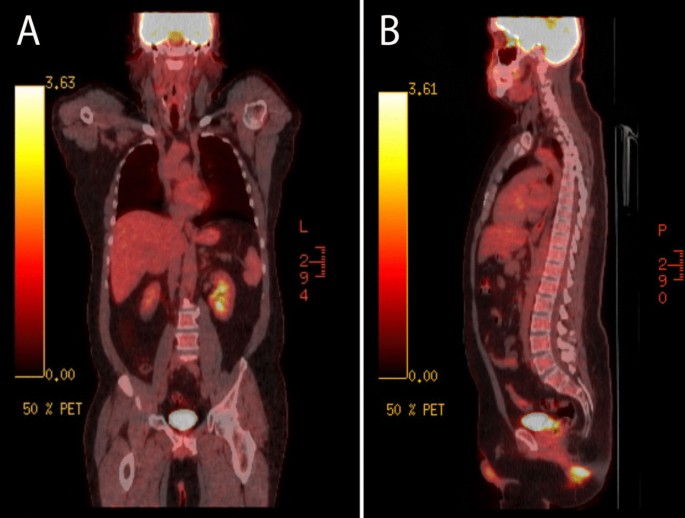

Three weeks later, the patient reported reduced pain and itching in his right lower extremity (RLE) and perianal area after using the topical zinc oxide cream. A positron emission tomography (PET) scan (Fig. 8) was also ordered to evaluate for any metastatic disease and failed to show any disease spread. Given the extent of disease that involved the anal margin, the patient would not have been a candidate for local excision as this would cause an anal stricture. The only surgical option would have been an abdominoperineal resection, committing the patient to a permanent end colostomy.

We depended on the clinical picture to guide the patient’s disease management. The patient’s perianal lesion has been stable since its eruption in June 2019, with no systematic metastasis despite the lack of chemotherapy or surgical intervention. In addition, the patient has a 3-year history of DI, which has been reported as an inaugural sign of LCH [30]. Between 10% and 16 % of LCH patients have DI [30, 31]. This is due to a particular predilection of LCH to the hypothalamic–pituitary axis (HPA), where monoclonal proliferation of aberrant histiocytes accumulates in and infiltrates into the axis. MRI findings associated with DI have been described. Typically, the pituitary stalk thickens, and it can progress into a mass lesion that extends to the hypothalamus and pituitary gland, and the normal hyperintensity of the pituitary is therefore lacking [32]. In Prosch et al.’s retrospective study, DI onset preceded LCH diagnosis in 43% of patients, and in 51% of these patients, LCH could be diagnosed within 1 year of DI [30]. There was no reported association between DI and LCS in the literature [22,23,24, 27, 31]. Thus, the patient was diagnosed with LCH based on his stable cutaneous lesion, history of DI, and benign cellular morphology.